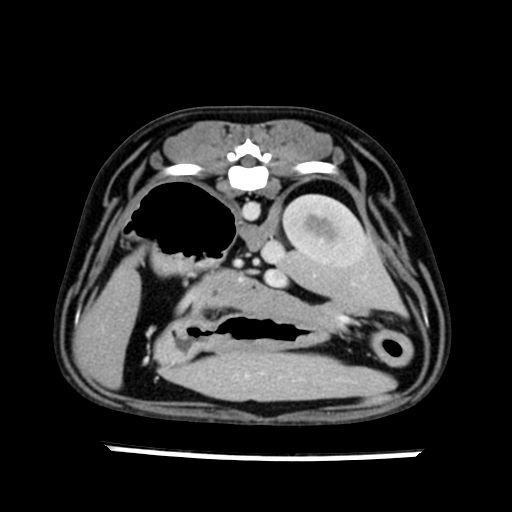

prescritto esame TAC

sequenza immagini limitata al fegato reni e surreni

le immagini ecografiche rispetto alla tac datano circa 7 mesi prima ,le surrenali sono normali nonostante il test acth sia risultato positivo .all’esame TAC dopo diversi mesi risultano aumentate armonicamente nel volume e si individua un forte sospetto di adenoma ipofisario .

sospetto adenoma ipofisario vs. meno probabilmente meningioma della base; intertiziopatia polmonare; lesione espansiva epatica, verosimilmente del lobo laterale sinistro, di sospetta natura neoplastica; lesioni spleniche di natura da definire; iperplasia/ipertrofia delle ghiandole surrenali, bilateralmente; vertebra di transizione del rachide toracico; tenosinovite cronica del muscolo bicipite brachiale di destra.